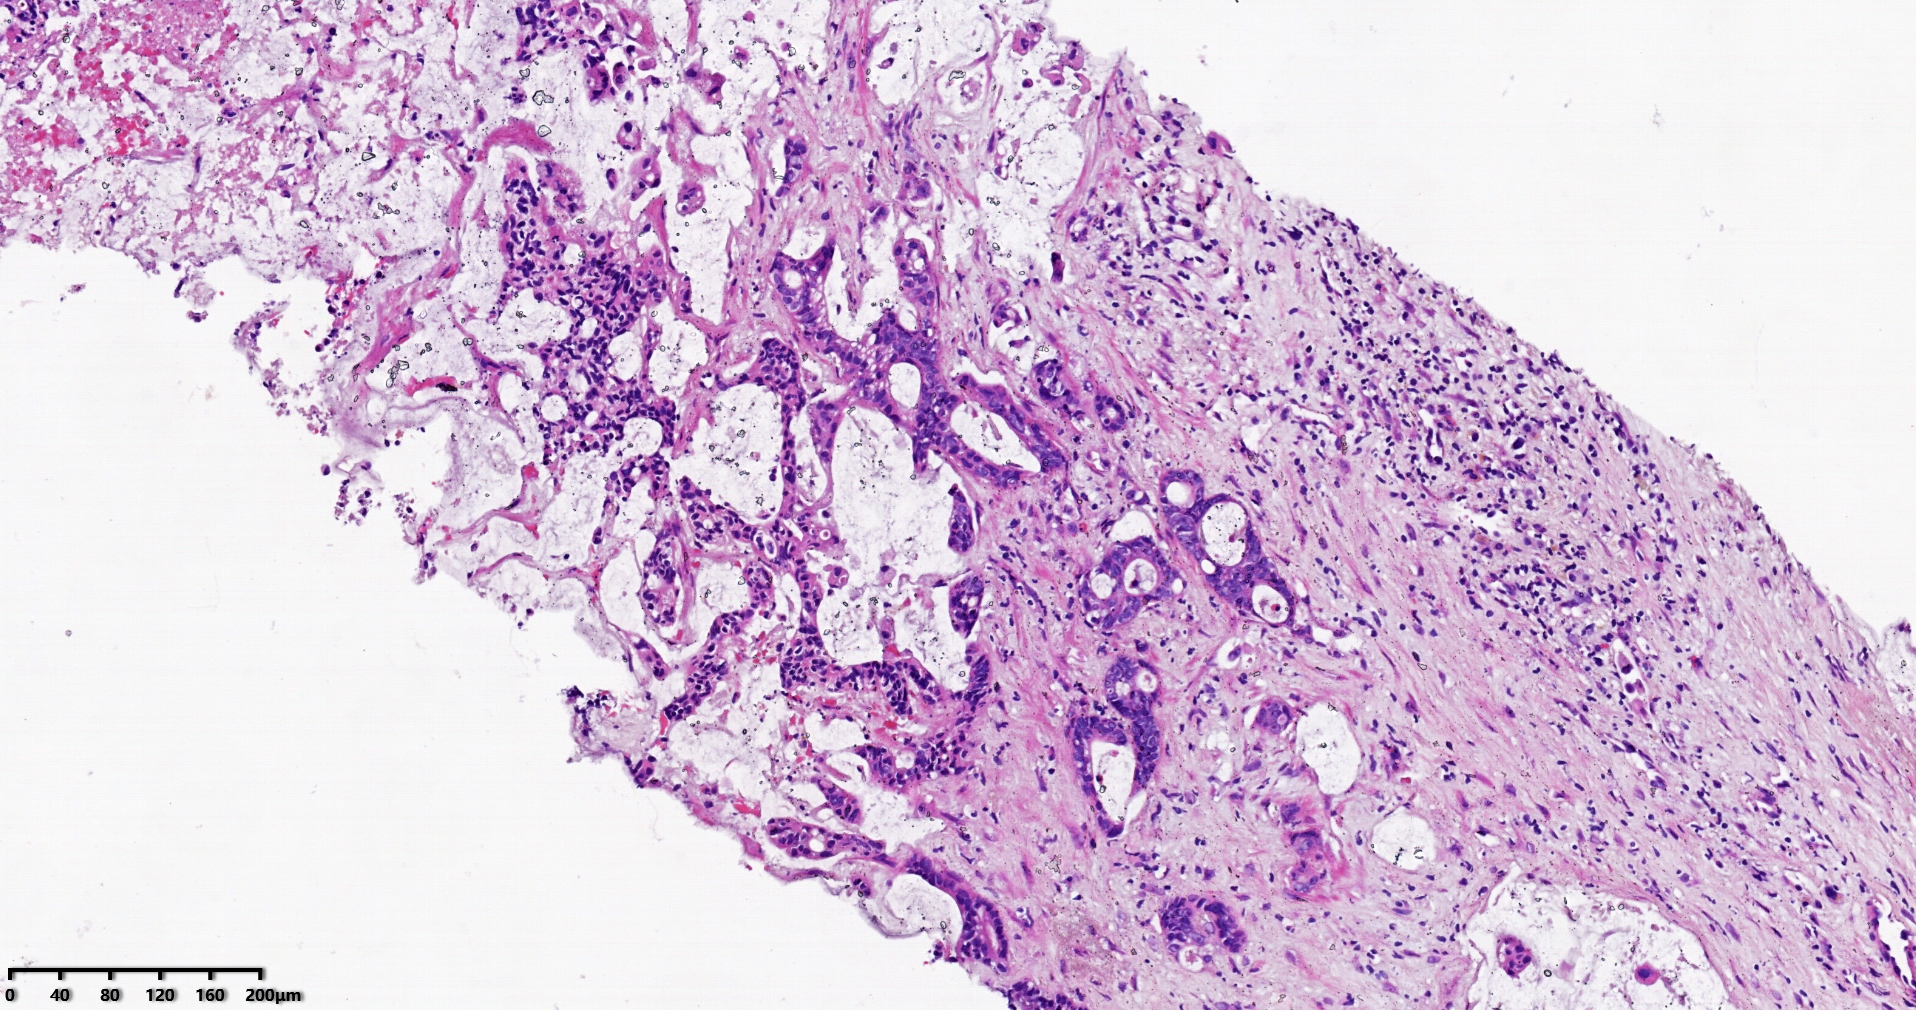

标本名称肝脏穿刺

大体所见灰白灰红色穿刺活检组织两条,长1.7-1.9cm,直径0.1-0.2cm。

考虑符合:肝内胆管癌

考虑转移性黏液腺癌,消化道来源可能,建议做免疫组化,排除胆管源性。